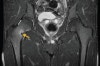

MRI : 고관절 피로골절(Stress fracture of the hip)

MRI는 매우 감수성이 높은 검사이며, 압박을 받는 면(compression side)과 긴장이 가는 면(tension side) 병변 간의 감별에 유용합니다.

피로골절이 의심 되지만 X-ray에서 정상인 환자는 MRI 시행을 고려하여야 합니다.